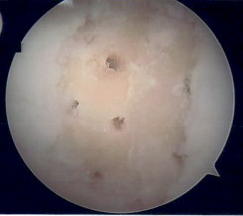

Microfracture

Microfracture of trochlea chondral defect

van Tuijn et al Cartilage 2023

- systematic review of microfracture

- worse outcomes in PFJ than in knee condyles